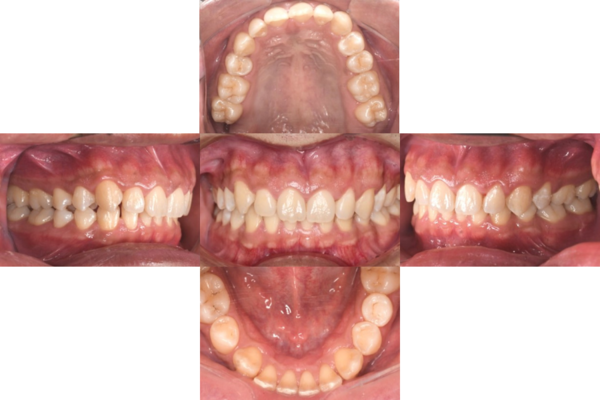

症例

症例1

Before

after

基本情報

年齢・性別 52歳・男性

主訴 主訴:久しぶりの歯医者なので歯石をとってほしい

治療部位:全顎

治療内容 1.歯磨き指導、歯肉縁上の歯石除去

2.歯磨きの確認、指導(磨けるようになるまで)

3.歯磨きの確認、指導、歯肉縁下の歯石除去(SRP)

4.PMTC

5.再評価、歯磨きの確認、指導

治療期間 1日

治療費 合計17,560円

・内訳

1、歯周基本検査・歯磨き指導、縁上スケーリング:1,800円

2、歯周精密検査・SRP(スケーリング・ルートプレーニング)、歯磨き指導:2,130円

3、SRP、歯磨き指導:3回(1,530円×3回)

4、PMTC、全顎再スケーリング、歯磨き指導:5,500円(自費診療)+1,260円

5、再評価(歯周精密検査)、歯磨き指導:2,280円

※PMTC以外、保険診療3割負担

(2023年5月現在現在)

リスク・副作用 ・毎日の歯磨きが不十分だと歯石を除去しても再度歯石がついてしまう

・最初は歯磨きのときに出血してくることがあるが、細菌が減って歯茎が引き締まってくると徐々に出血は落ち着いてくるため痛みがなければ辛抱強く磨いてもらう

・歯周病は時間をかけて静かに進行する病気なので、歯周病を治すにはそれなりに期間がかかる、すぐには治らない

・歯ぐきが引き締まると歯茎が下がり歯間に隙間ができる可能性がある

治療方針 一時的な治癒ではなく、将来的にこの治療が活かされるよう、患者さん自身である程度自己管理ができるようになることを目標とした

特記事項 ふつうのブラシと電動歯ブラシ使用(ブラウン丸型使)

歯間ブラシを1日1回は最低でも使って頂いた

担当者所見 あまり器用な方ではなかったため、決まったところがいつも磨けず奥歯に歯間ブラシがなかなか入れられませんでしたが、歯間ブラシのサイズを変えてみたり、内側から入れてみたりと試行錯誤してなんとかある程度磨けるようになりました。

その結果、出血が100%から7%へ激減することができました。

ただSRPをしただけではここまでの結果は出なかったと思います。

それほど日々のセルフケアが重要だということを再認識しました。

歯周ポケットが残っている部位、出血がある部位に関しては引き続き歯磨きを念入りに行なってもらう。

症例2

歯周病検査(治療前)

歯周病検査(治療後)

レントゲン写真

年齢・性別 41歳・男性

主訴 主訴:歯ぐきから出血する

治療内容 1.歯周ポケット検査、資料取り(レントゲン写真14枚・口腔内写真)、歯磨き指導

2.歯磨き指導チェック、縁上の歯石除去

3.縁下の歯石除去4回

4.再評価(歯周ポケット検査・レントゲン写真14枚・口腔内写真)

5.メインテナンス

治療費 合計:14,160円

内訳(全て保険診療3割負担)

・初診検査、歯磨き指導、縁上の歯石除去:3,630円

・レントゲン写真、縁下の歯石除去①:3,040円

・縁下の歯石除去②:1,530円

・歯磨き指導チェック、縁下の歯石除去③:2,070円

・縁下の歯石除去④:1,530円

・再評価:2,360円

(2022年5月現在現在)

担当者所見 全体的に出血が見られたのと、奥の歯ぐきは炎症があり歯周ポケットが深かった為、まずは歯ブラシの当て方+歯間ブラシ3Sサイズを使用して頂き炎症を落ち着かせました。

両方毎日使用して頂いた為、スムーズに歯周病治療を行うことができました。毎日のホームケアが不十分だと、なかなか結果に繋がらず、治療期間も長くかかってしまう為、患者様の協力が歯周病治療を成功させるためにはかなり重要になっていきます。

そして一度病気になった歯ぐきは再発しやすい為、今後は3ヶ月に1度の定期的なメインテナンスで、この状態を維持できるよう一緒に管理していきます。